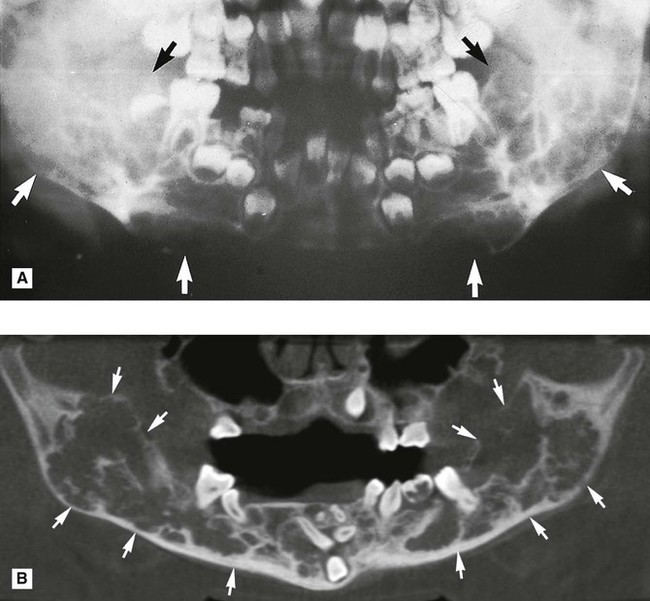

Cherubism (Fig. 26.20)

• Age: Children, 2–6 years old.

• Site: — Angle/posterior mandible – bilateral

• Size: Variable, up to several centimetres in diameter, and may fill the whole jaw.

• Radiodensity: Radiolucent with internal radiopaque septa producing a multilocular appearance.

• Effects: —Adjacent teeth – gross displacement of deciduous and permanent teeth, occasionally resorbed, deciduous teeth sometimes exfoliated early